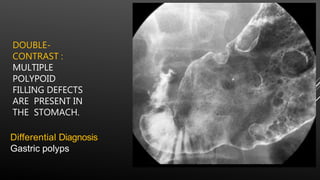

DOUBLE-

CONTRAST :

MULTIPLE

POLYPOID

FILLING DEFECTS

ARE PRESENT IN

THE STOMACH.

Differential Diagnosis

Gastric polyps